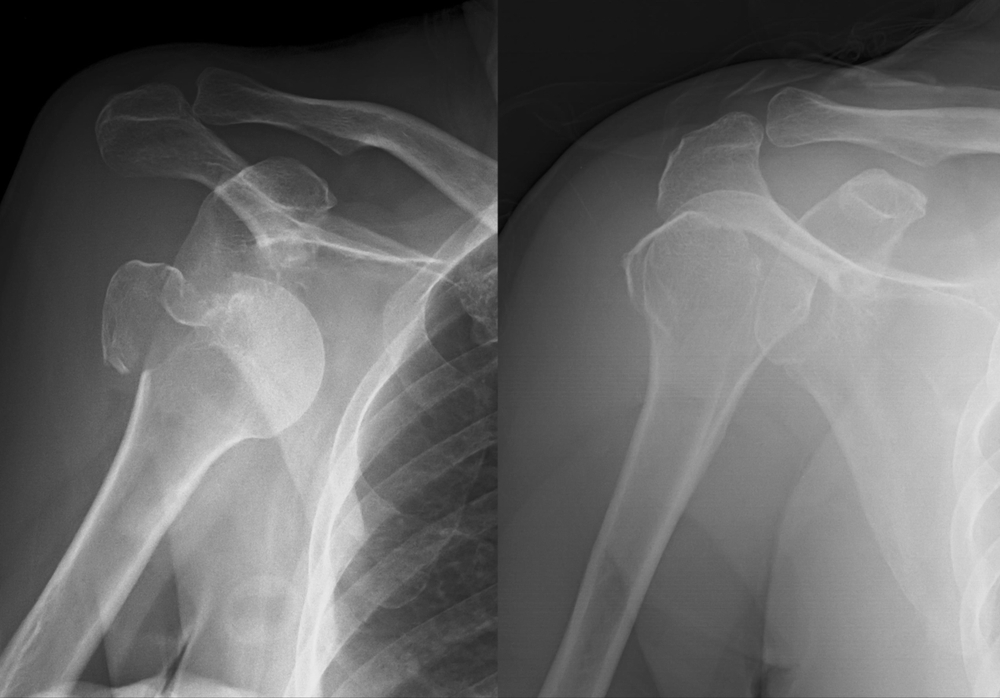

Como é a recuperação da cirurgia para a luxação do ombro?

12 abril, 2023

A cirurgia de luxação do ombro deve ser feita quando há lesões significativas nas estruturas da articulaçãoRecebe o nome de “luxação do...